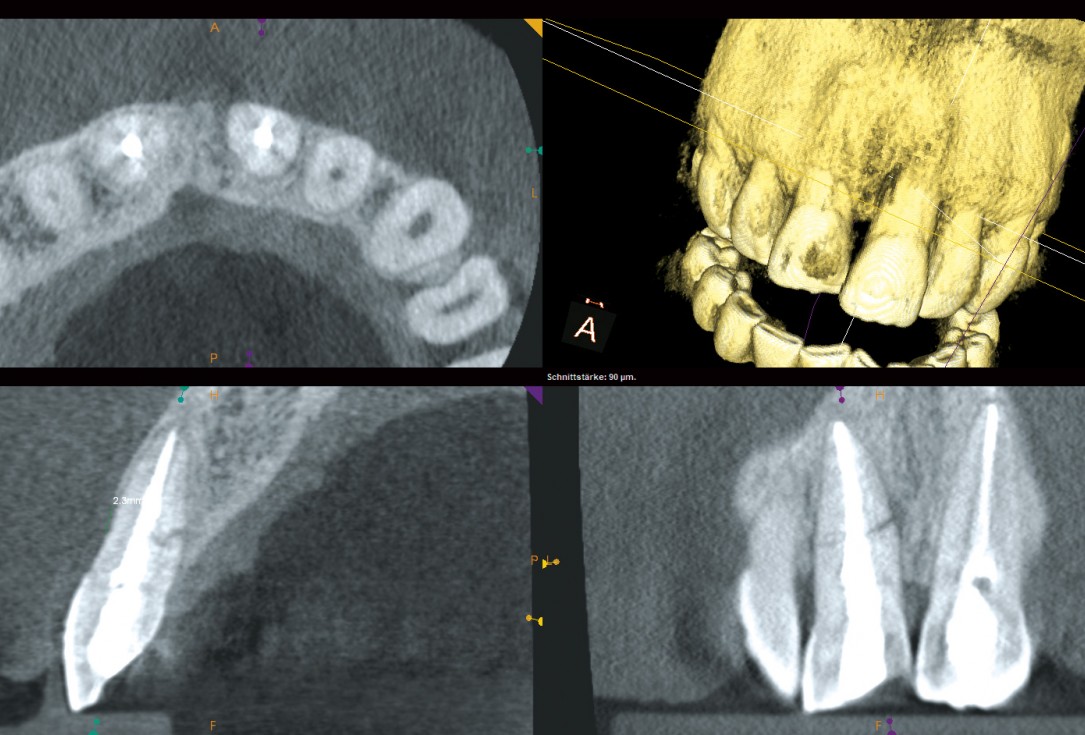

04/18 - CBCT scan after tooth extraction

Block augmentation with maxgraft® and cerabone® – PD Dr. Dr. F. Kloss